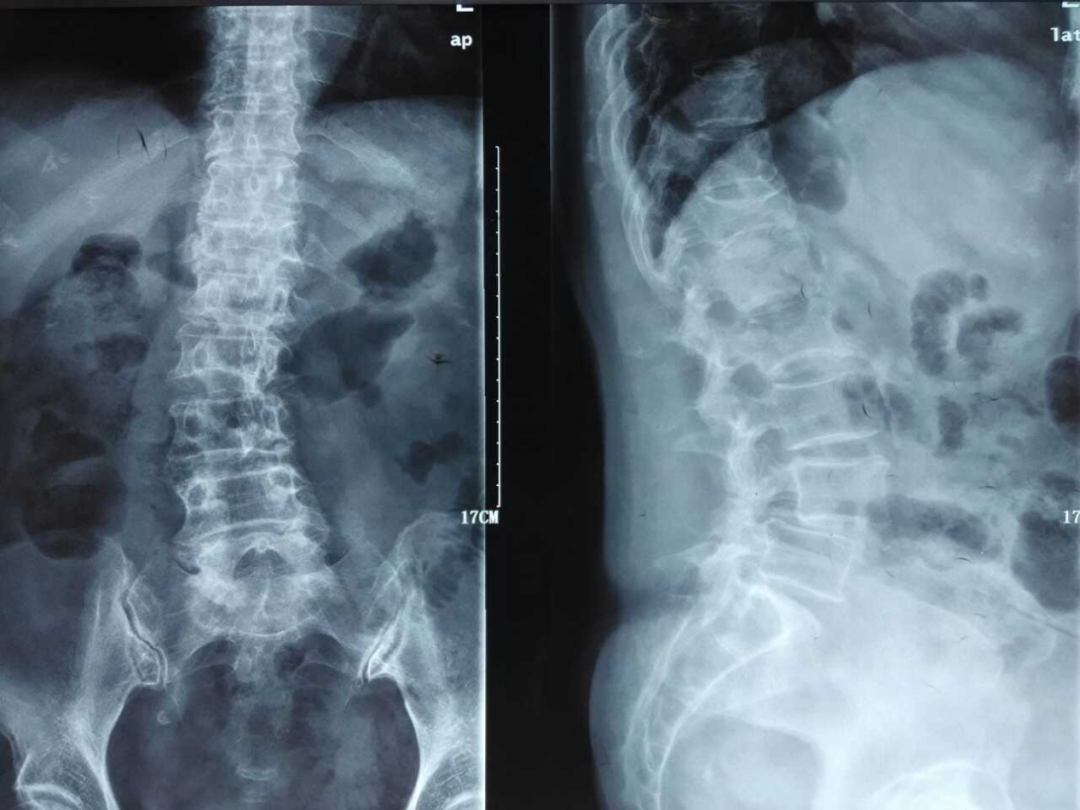

2、利用X线平片发现椎体压缩性骨折(每个医院包括社区均有):

脆性骨折是指受到轻微创伤或日常活动中即发生的骨折,老年男性椎体骨折的患病率与女性相当,椎体骨折的防治在男女两性同等重要。

常规进行X线胸腰椎正侧位摄片漏诊率高,患病率高(上海社区60岁以上17%,建议对50岁以上腰背部疼痛者常规摄片,及早发现椎体骨折。

二、骨质疏松症如何进行影像学检查

X线平片是检出脆性骨折,特别是胸、腰椎压缩性骨折的首选方法。常规胸、腰椎X线侧位摄片的范围应分别包括胸4至腰1和胸12至腰5椎体,基于胸、腰椎侧位X线影像并采用Genant目视半定量判定方法,椎体压缩性骨折的程度分类如下:

X线检查:L2压缩性骨折椎体骨质疏松,头颅未见异常。